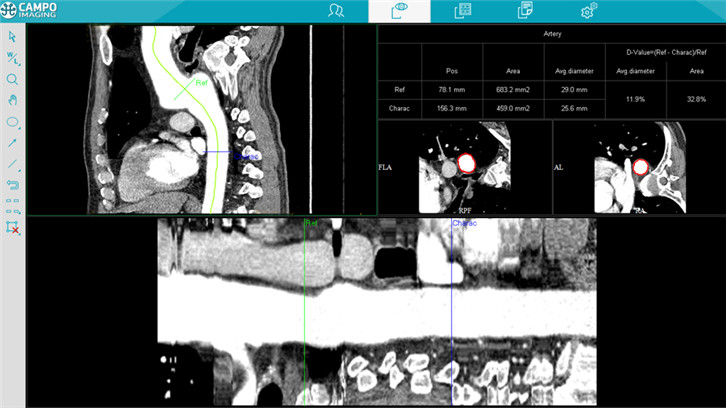

血管分析